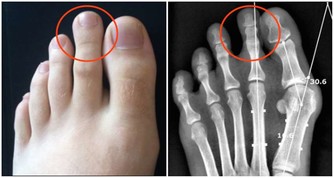

1.上肢神經卡壓:一是拇、食、中指的麻木疼痛,常有夜間麻醒史,醒後活動可好轉。

嚴重者可伴有手部肌肉萎縮,影響手的精細動作,

這是因為正中神經在腕部受到壓迫,即所謂的「腕管綜合徵」;

二是環、小指的麻木疼痛,也可有夜間麻醒史,

嚴重者伴有肌萎縮,環、小指的屈指力下降,影響精細動作。

這是因為神經在肘部受到卡壓,即所謂的「肘管綜合徵」。